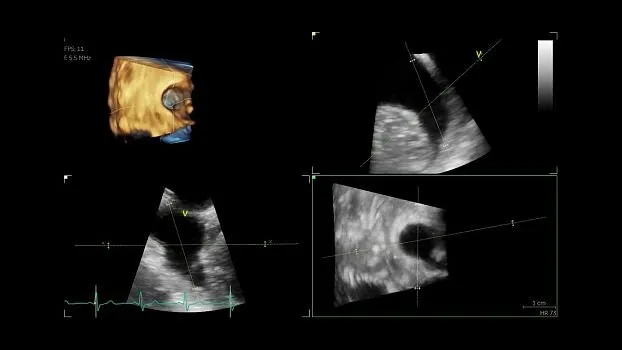

- Бескомпромиссный уровень качества визуализации как в двухмерном режиме, так и в режиме объемной реконструкции, а также гарантируя высочайшую чувствительность при цветовом картировании кровотока и допплерографии.

- Беспрецедентное пространственное разрешение и детализацию.

Экспертное качество изображений при проведении 2D TTE исследований и при обычной трансторакальной эхокардиографии дает возможность проводить сложные кардиологические исследования и получать достоверные результаты для назначения эффективного лечения.

- Auto LVQ — функция, которая дает возможность двумя нажатиями кнопок разместить точки исходных границ эндокарда, основываясь на данных, полученных от 4D TEE датчика. Данный инструмент количественного анализа позволяет отобразить в графическом виде полные 4D данные, используя технику трекинга поверхности на базе каркасной модели.

- Изображение сердца в трех плоскостях с высоким временным и пространственным разрешением на основании данных одного сердечного цикла.

- 4D TEE — благодаря высокопроизводительной платформе cSound выполнение объемной чрезпищеводной ЭхоКГ стало ощутимо легче, понятнее и быстрее. Для вас открыты широкие возможности просмотра высокоточных изображений сердца во время оценки его функций и диагностики в условиях эхолаборатории, уверенное выполнение манипуляций под ультразвуковым контролем при катетеризации или инвазивных хирургических вмешательствах в операционной.

- FlexiSlice — функция, которая позволяет в реальном масштабе времени или режиме воспроизведения переключаться между объемной визуализацией и режимом получения произвольных срезов.